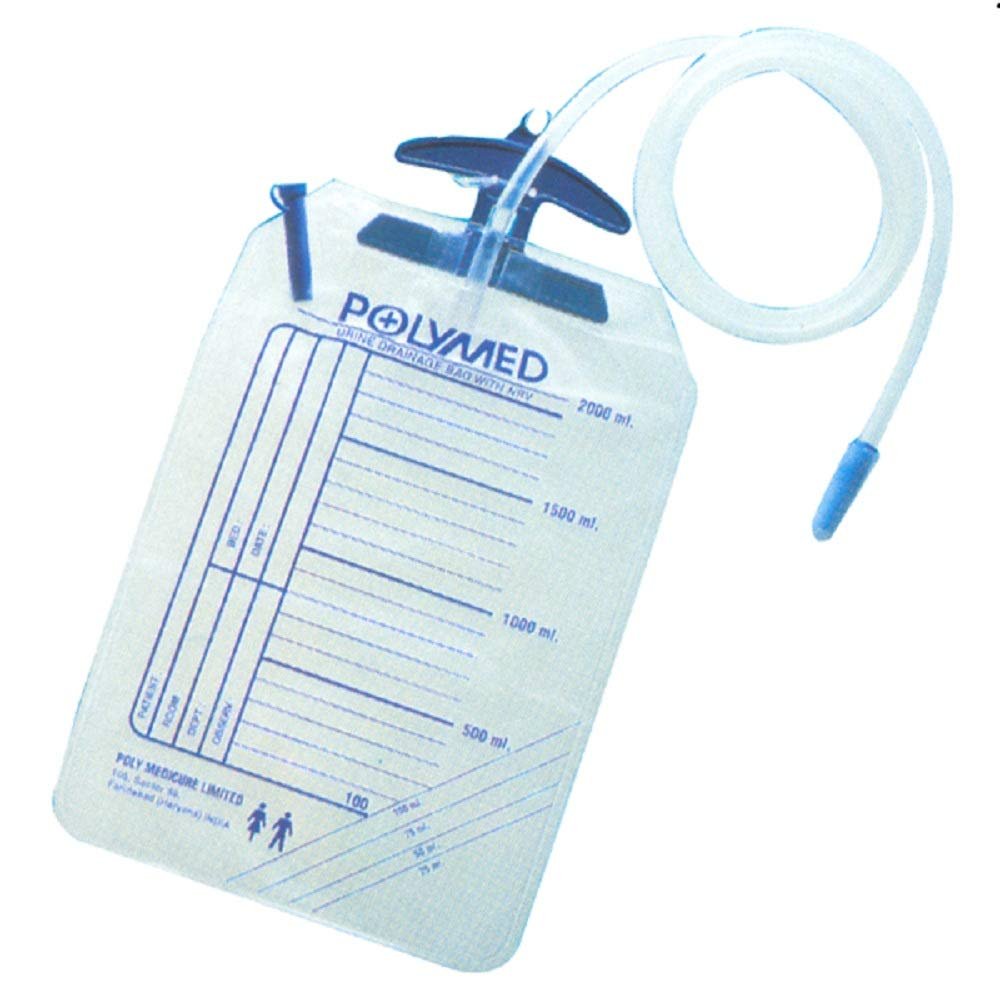

Urine Collection Bag With Bottom Outlet

Urine Collection Bag With Bottom OutletOur ProductsFrom SurgicaveUplode:9 months ago from India